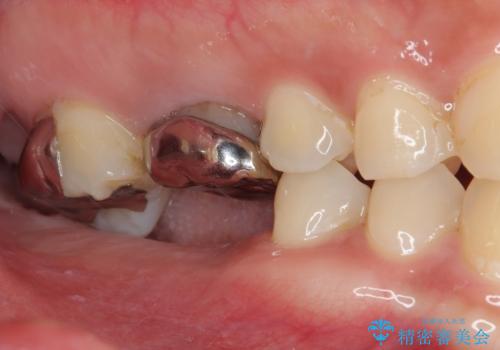

挺出歯を圧下してスペースを確保!目立たない部分矯正で下顎大臼歯にインプラント治療を実現